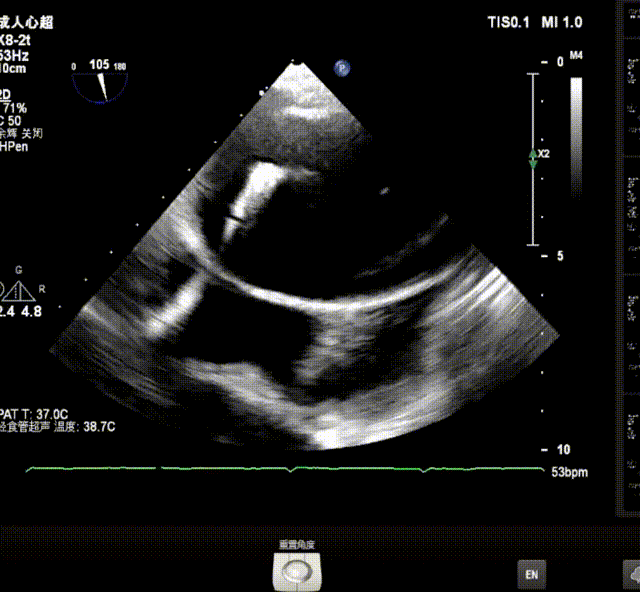

术前超声诊断:双房扩大,二三尖瓣中度关闭不全,二尖瓣P2P3偏P2区脱垂,主动脉瓣轻中度关闭不全,升主动脉增宽,TEER解剖难度分级:黄区,轻度肺高压。LVEF为73%。

X-plane视窗可见二尖瓣病变区脱垂,重度偏心性返流.

3D enface view示二尖瓣P2P3区瓣叶脱垂,偏心性返流